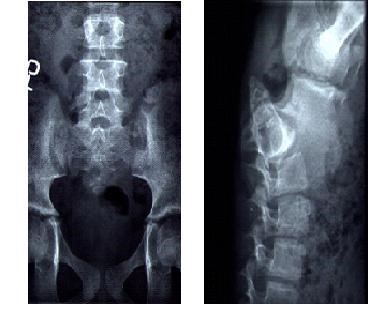

U 3-letniego dziecka stwierdzono niedorozwój kości krzyżowo-ogonowej (patrz zdjęcia poniżej). Jakie badanie powinno być wykonane w następnej kolejności?